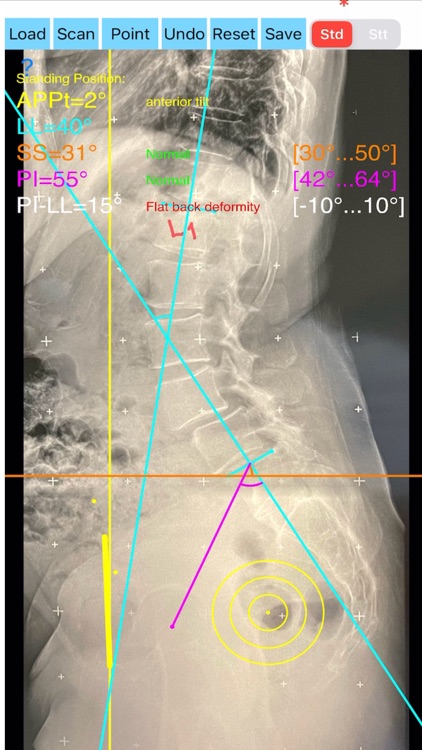

Evaluation of functional spinopelvic imaging in lateral radiographs in sitting and standing positions is of importance, especially in patient before total hip replacement surgery. Patients with concomitant hip and spine pathology undergoing primary total hip were identified as being at high risk for dislocation. Instability-prone patients arhtroplasty (THA) should appropriately assessed for the presence of deformity and abnormal spinopelvic mobility. The preoperative planning for THA should encompass evaluation of functional spinopelvic imaging in lateral radiographs in sitting and standing positions. Before planning cup position the surgeon should taken into account also anterior pelvic plane (APP) the coronal (functional) plane and the anterior pelvic plane tilt APPt or pelvic tilt and abnormal spinopelvic mechanics from standing to sitting.

The App is software aimed for orthopaedic surgeons, and allow to:

- mark certain points at the image of X-ray, and calculate at once the anterior pelvic plane tilt (APPt) or pelvic tilt , Pelvic incidence (PI), Sacral slope (SS), Lumbar lordosis (LL), Pelvic incidence Angle (PI) minus Lumbar lordosis Angle (LL)(PI–LL).

-to classify the patient into one of four Categories of the Hip-Spine Classification (1A,1B,2A,2B) by integrating spinal alignment (spinal deformity defined at PI-LL mismatch >10 degree(1)

-cases are categorised to group-specific recommendations for acetabular cup position respectively thus with minimal measurements will effectively identify the complex “hip-spine” THA patient at high risk for postoperative instability (1).

-According to measured parameters in standing and sitting lateral x- rays - based n a busy everyday practice, app offers a convenient way to perform radiographic measurements for spine, at the spinopelvic juncture - combing sitting and standing X-Rays, in a blink of an eye in front of your screen. The build in features of the app, allows results to be categorized and may help identify the complex “hip-spine” THA patient at high risk for postoperative instability and helps planning the optimum cup placement.